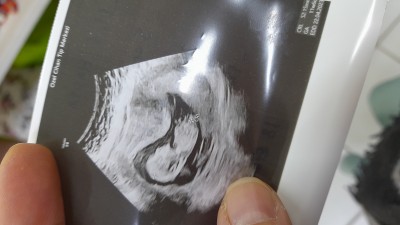

Hep bakar tahminde bulunurum cinsiyet için Bi de benm bebisime bakın da tahmin edin kiz mi erkek mi doktor net bisey söylemedi..

Gebelik haftası 12+3